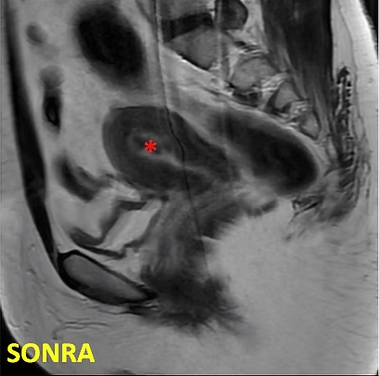

41 yaşında, kabızlık, gaz ve sık idrara çıkma şikayetleri var. Emar’da karını dolduran dev miyom (*) mevcut. Miyomektomi önerilmiş, ancak operasyonda rahimin alınabileceği söylenmiş. Embolizasyondan sonra dev miyomun ve bir başka küçük miyomun öldüğü ve küçüldüğü izleniyor. 7 ay sonra hasta şikayeti kalmamıştır.